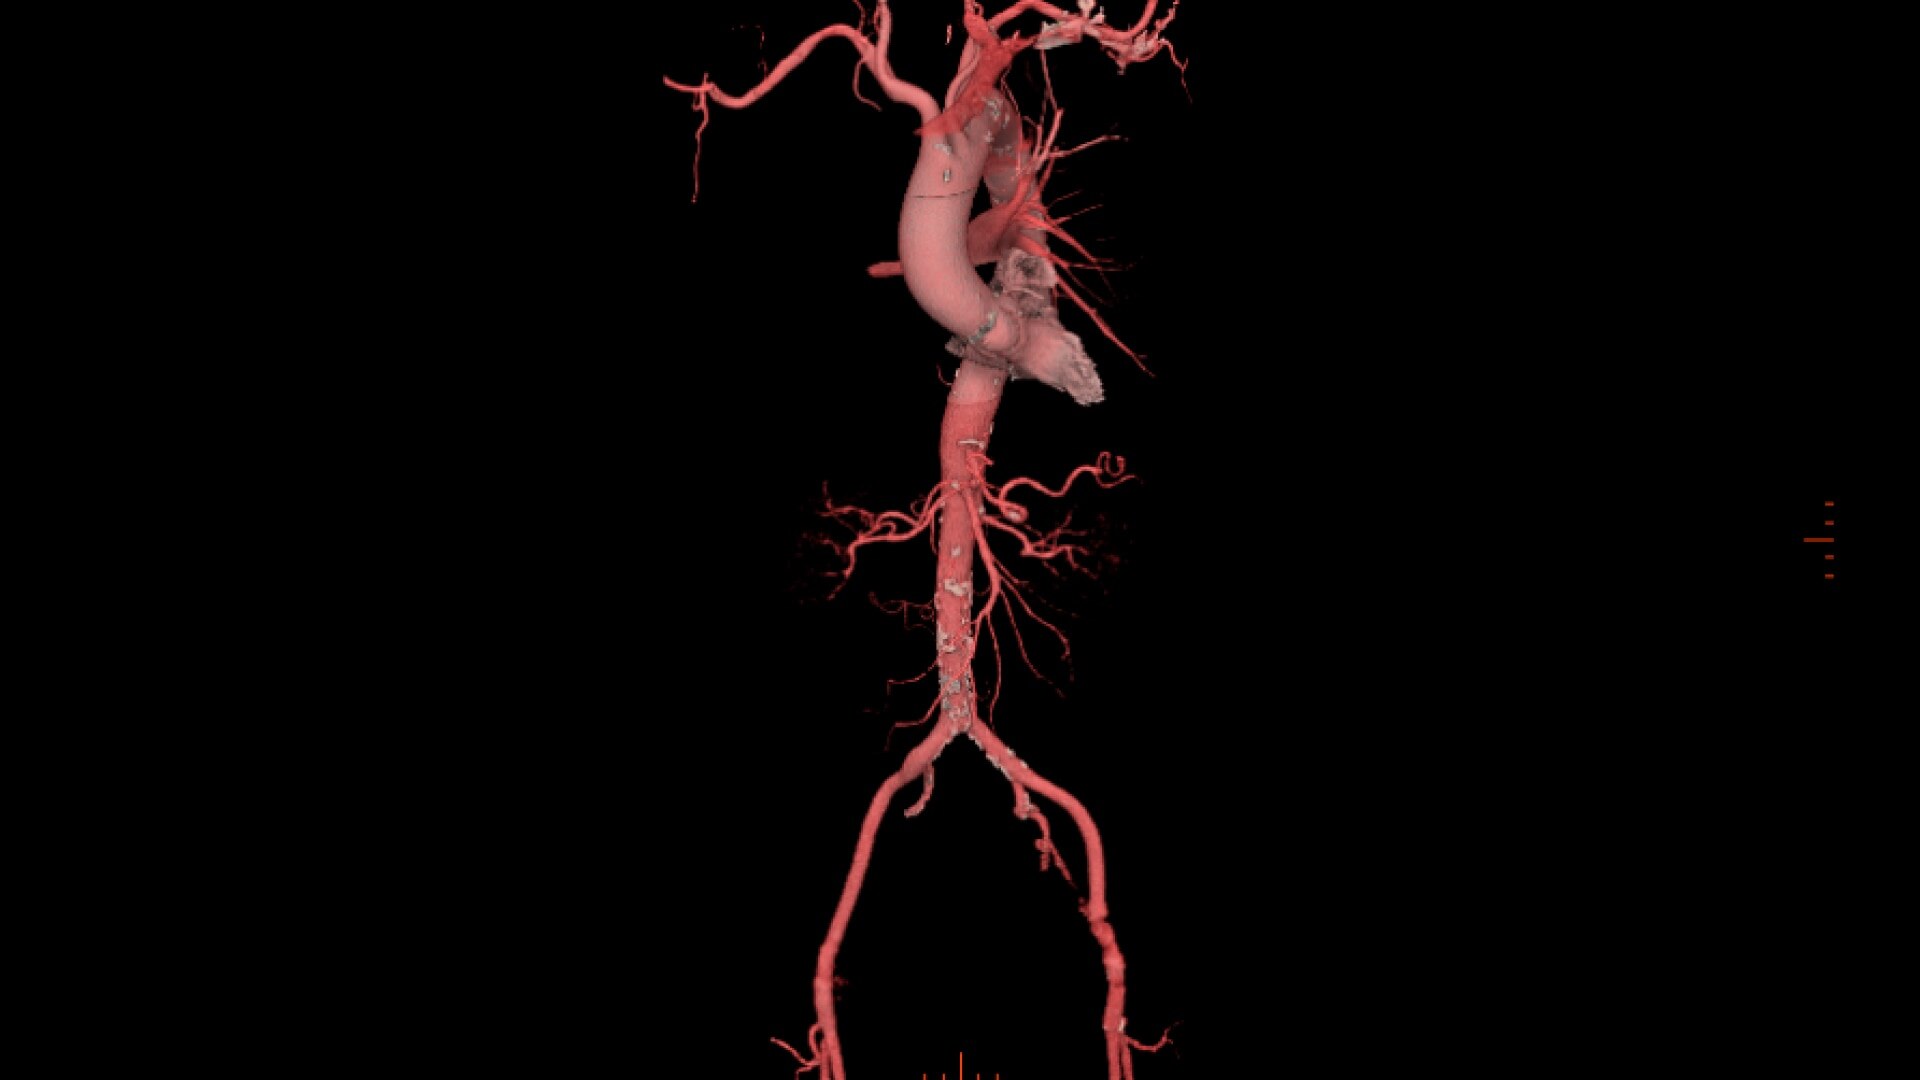

• Automatic centerline tracking for peripheral access planning